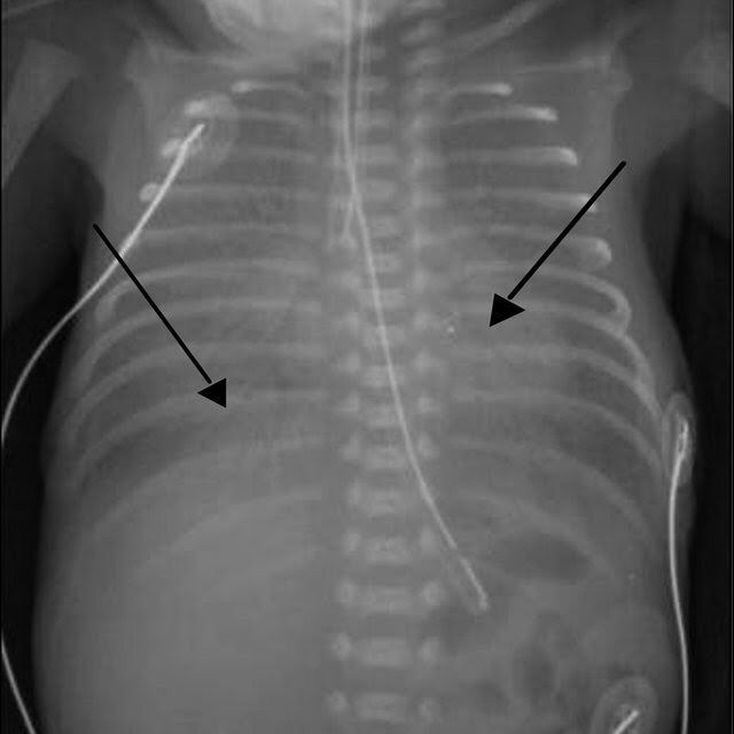

Infant respiratory distress syndrome

We can see “ground glass” appearance, which represents diffuse microatelectasis, and air bronchograms (arrows). Ethiology: Preterm labor-low surfactant-atelectasis.